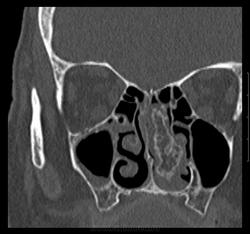

Женщина 1954г.р. обратилась к доктору 20.06.13г. с жалобами на головные боли, головокружение, тошноту. DS: энцефалопатия сложного генеза, ГБ, ШОХ. Отправлена МРТ г.м от 19.07.13г.- общая сообщающаяся гидроцефалия заместительного характера, TR клетках решетчатой кости, рекомендовано КТ. На приеме у ЛОР 26.0713г.: жалобы на затруднение носового духания; объективно- полипозная ткань в нос.пазухах слева. После проведенного КТ 30.07.13г. позвонил пациентке, говорит что примерно раз в три месяца бывают носовые кровотечения даже в горизонтальном положении. Что думаете коллеги?

Вот ее снимки.

Дополнительное образование в носовых раковинах слева ( или справа? у нас в МРТ это левая сторона ) с признаками обызвествления.Носовые раковины разрушены.Думаю, что точно нужно оперировать.

Левая сторона. Дело не в том, что нужна или нет операция. По моему это добро, но какое??? Хондромиксоидная фиброма? хондрома? Прилежащие костные и хрящевые структуры без признаков деструкции. У образования костно- хрящевая основа. Или я не в ту степь думаю...)